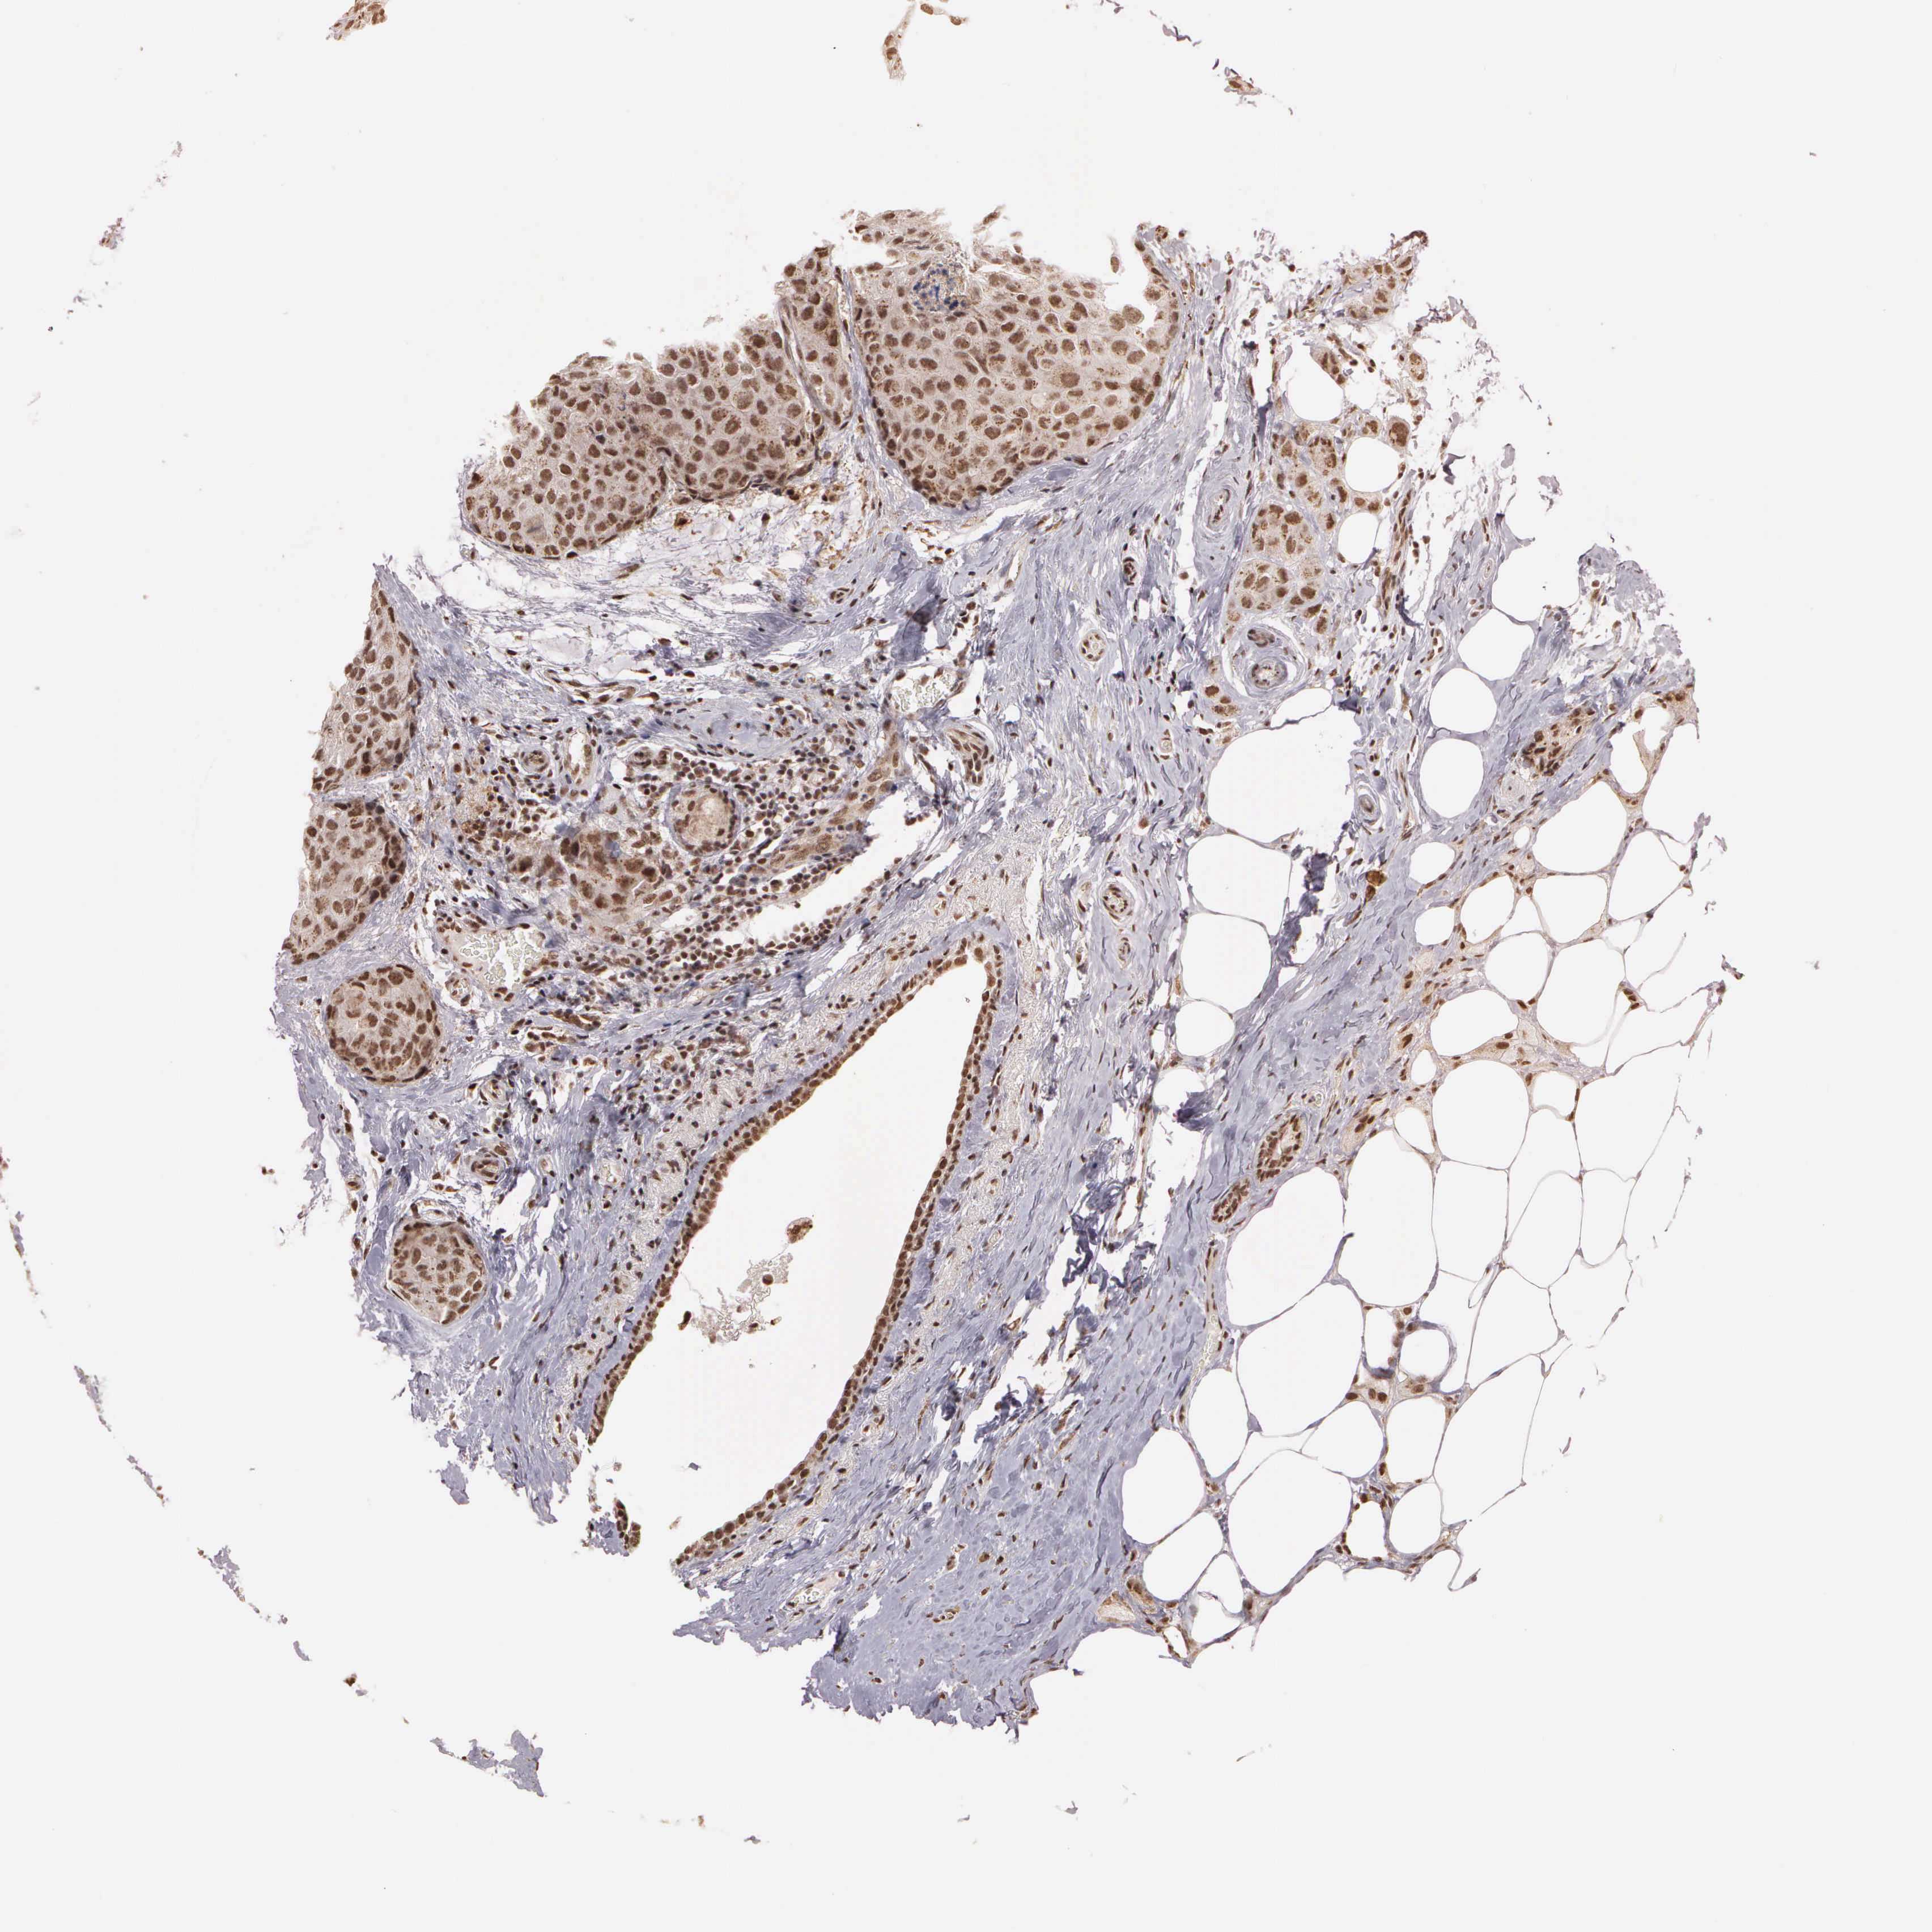

CANCER BREAST CANCER Show tissue menu

Breast cancer

Human cancer